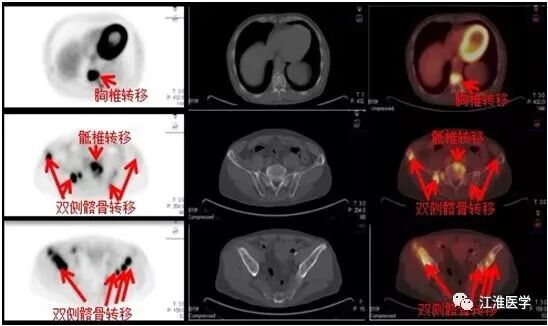

老张的结果,可想而知,下面的图诉说着血淋淋的故事:

图中左侧的黑白图除了大脑,心脏和膀胱外其余的黑点全是肿瘤病灶,右边的十字指示的是腮腺的复发的恶性肿瘤